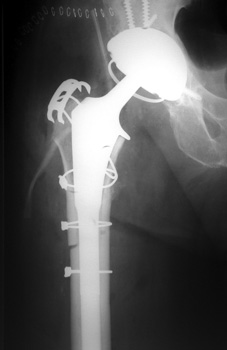

Control perforation lateral femoral cortex, reduced by cerclage cables. A control perforation of the lateral femoral cortex was performed in this revision total hip replacement to facilitate removal of the old femoral prosthesis. It is reduced by cerclage cables.